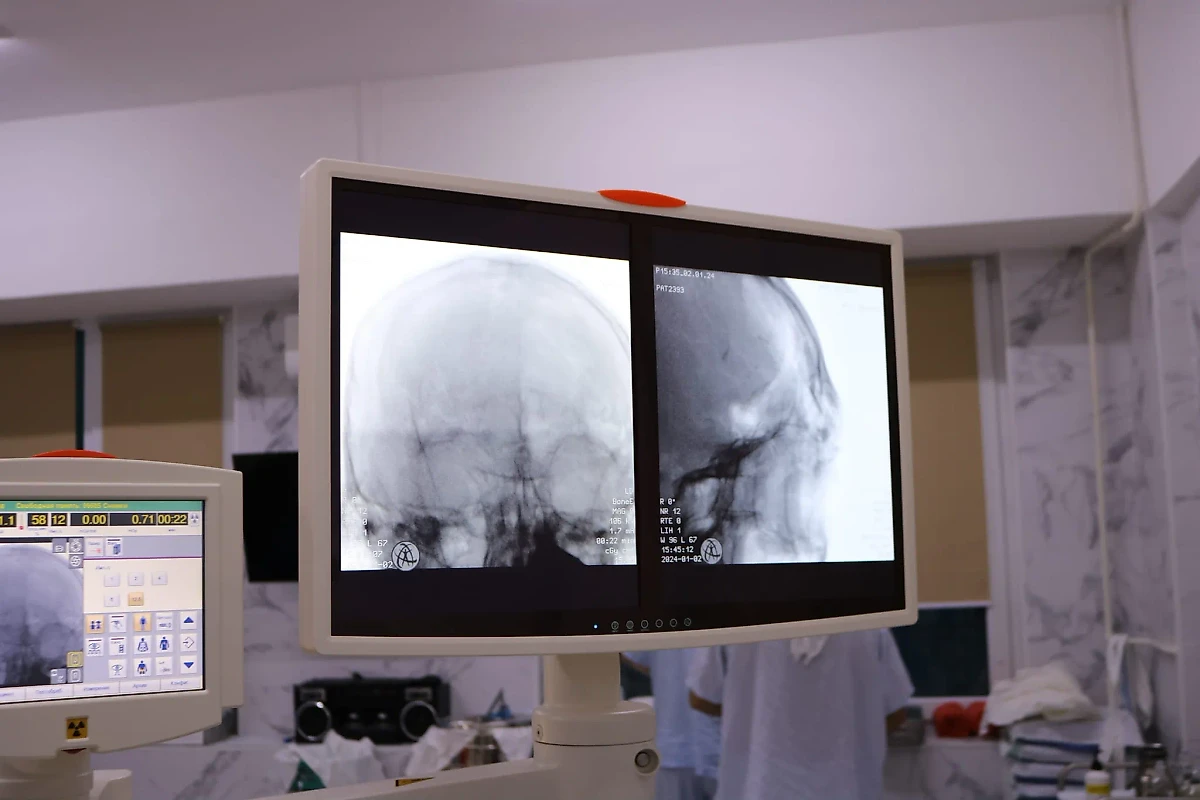

Снимок черепа пациента Бельцкой больницы с пулей в мозге. Фото © Facebook (заблокирован в России, принадлежит компании Meta, признанной в РФ экстремистской организацией) / IMSP Spitalul Clinic Bălți

Правоохранители отметили, что 26-летний пострадавший беспорядочно стрелял у себя в квартире. По информации ведомства, он спустил курок не менее шести раз, последняя пуля отрикошетила ему в голову и застряла в мозге.

Пациента доставили в тяжёлом состоянии, все жизненные показатели были нарушены. Врачи провели нейрохирургическую операцию, им удалось вытащить пулю из головы пациента. Сейчас он находится в тяжёлом, но стабильном состоянии.